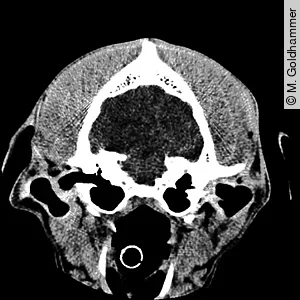

- Bei der computertomografischen Untersuchung des Schädels (Nativ, mit Früh- und Spätkontrastmittelgabe) wurden ebenfalls unauffällige Befunde erhoben.

- MRT/CT: In der bildgebenden Diagnostik stehen MRT/CT-Untersuchungen des Gehirns zur Verfügung. Damit können in manchen Fällen Veränderungen am Thalamus, den Basalkernen, der zerebralen weißen Substanz und dem Ventralhorn des Hals- und Rückenmarks aufgezeigt werden. Solche Veränderungen waren in der hiesig durchgeführten CT-Untersuchung jedoch nicht nachweisbar.